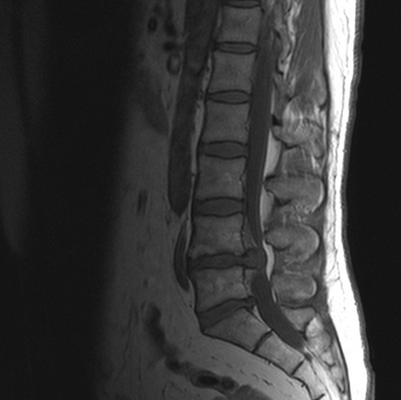

Что лучше - КТ или МРТ пояснично-крестцового отдела позвоночника?

Если причиной обращения в диагностический центр является боль в пояснице, то следует сделать МРТ пояснично-крестцового отдела позвоночника, поскольку она покажет изменения как в костных, так и мягких тканях. Если у вас уже есть первичный диагноз, то решение о том, КТ или МРТ пояснично-крестцового отдела позвоночника нужно делать, должен принять лечащий врач на основе собранного анамнеза.